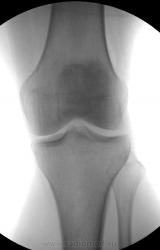

Вашему вниманию начало. Женщина. 40 лет. Травма - падение на колено пару недель назад. Жалобы на боли.

Суть примера - вариант теневой картины складок одежды в рентгеноском изображении.